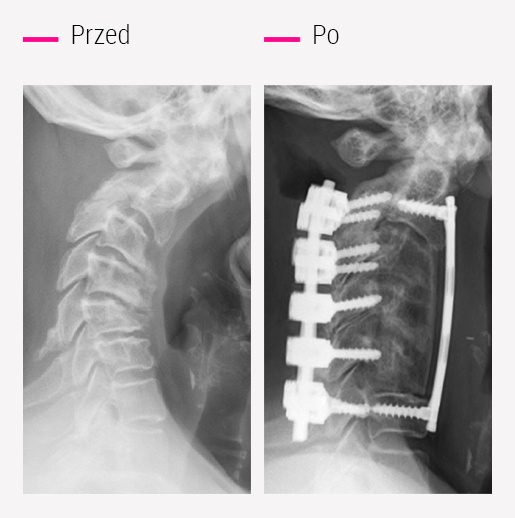

Złożone operacje kręgosłupa

CCV w Montpellier jest referencyjnym ośrodkiem zajmującym się leczeniem złożonych zwyrodnień kręgosłupa: deformacji, guzów, następstw urazów i nieudanych operacji

Opatentowana procedura chirurgiczna: Metoda tomografii przedimplantacyjnej

Ośrodek CCV Montpellier stworzył unikalny proces współpracy radiologa i chirurga w celu sterowania umieszczaniem implantów, który jest bardzo skuteczny w skomplikowanych, powtórnych operacjach.

Zabieg rozpoczyna się od umieszczenia pinów pod kontrolą tomografii komputerowej w celu optymalizacji trajektorii implantów. Dokładność tomografii pozwala radiologowi na systematyczne utrzymywanie bezpiecznej odległości od rdzenia kręgowego, nawet w przypadku najcięższych deformacji.